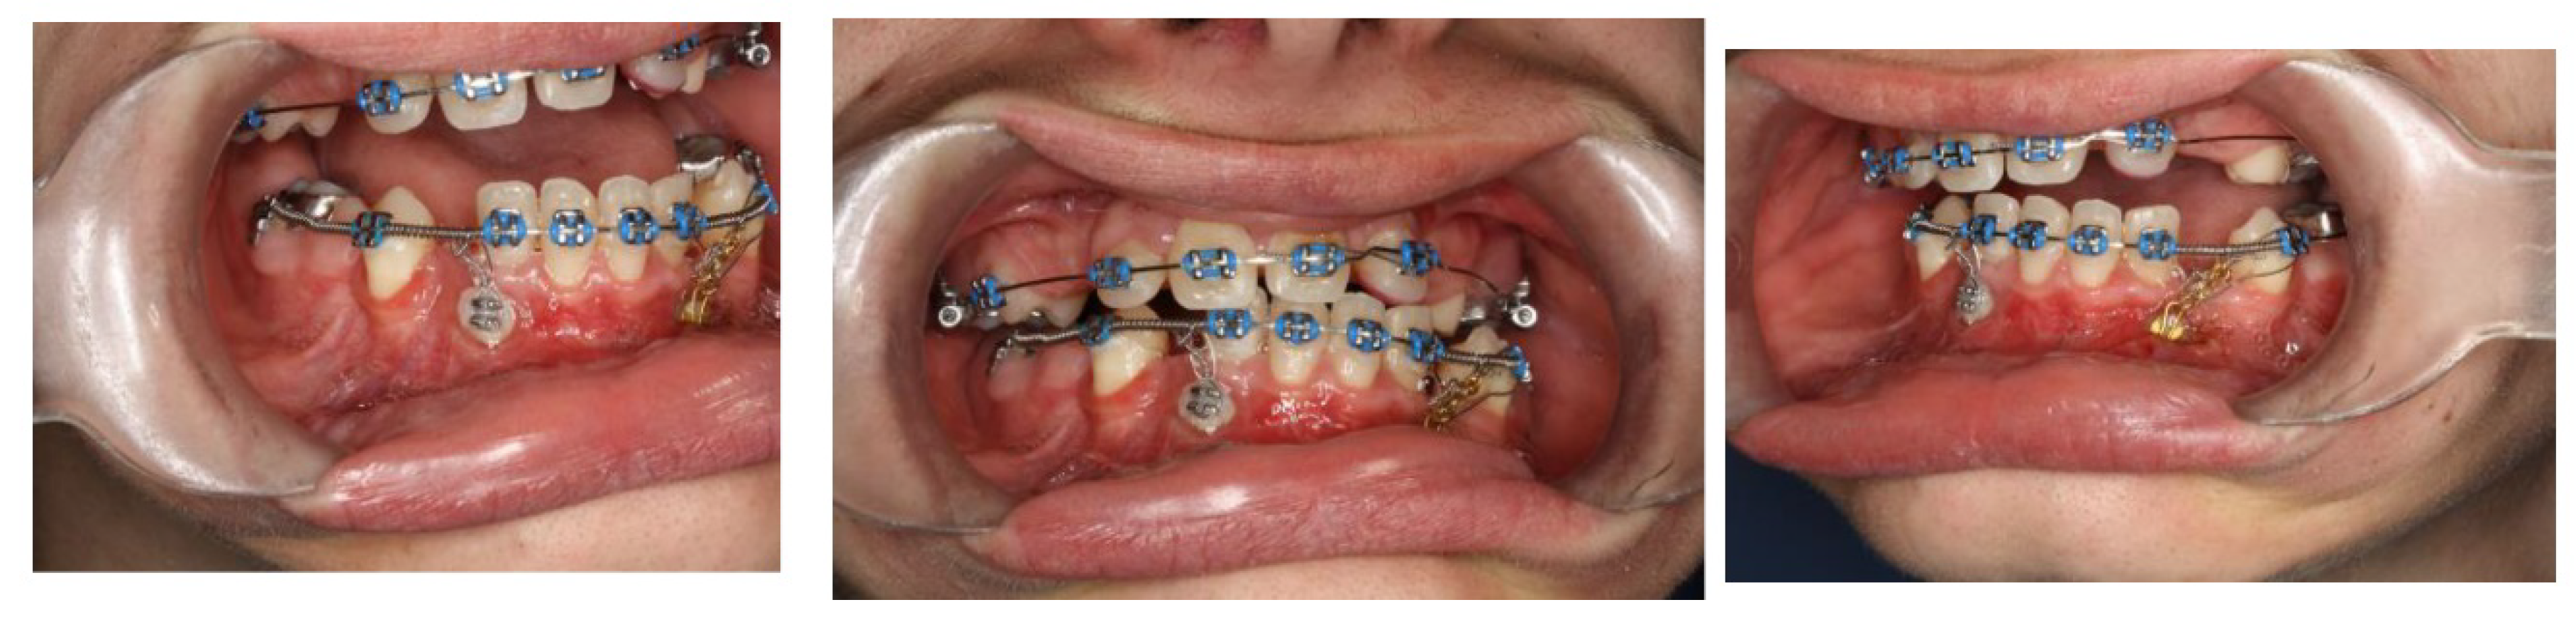

Surgical Intervention 4 (Local Anesthesia)

In January 2022 a surgical exposure in local anesthesia of 33 and 43 was provided, and the attachment was bonded immediately. The canines were encumbered with light distal forces to avoid interference of the canine crowns with the roots of the lower incisors. (Figure 16)

Figure 15. CBCT transverse section on the level of lower incisors - August 2021.

Figure 16. Top 3 pictures : Intraoral photographs after surgical exposure of the lower canines in January 2022. The brackets were bonded immediately, the same as the force loaded. Bottom pictures were taken in January 2024, after surgical exposure of teeth in the upper right and left quadrant in March 2023.